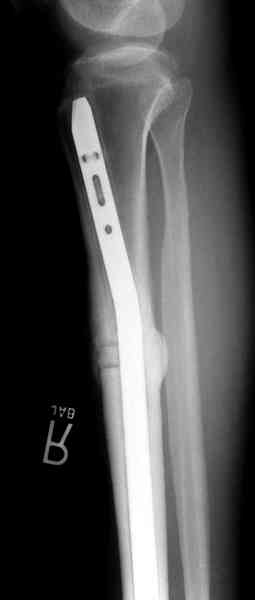

conference мы разбирали похожий случай, ложный сустав большеберцовой кости после резекции опухоли.

К нашему онкологу-ортопеду обратился больной с жалобами на боли в голени, из рассказа - год назад была сделана биопсия большеберцовой кости, но название заболевания "не запомнил”.

Оперирован в военном госпитале с заменой сегмента

аллокостью большеберцовой кости и после демобилизации явился для постоянного наблюдения по месту жительства.

Наши имели проблему со сращением, пришлось им сделать динамизацию, дополнительную аутопластику.

Снимки представлены.